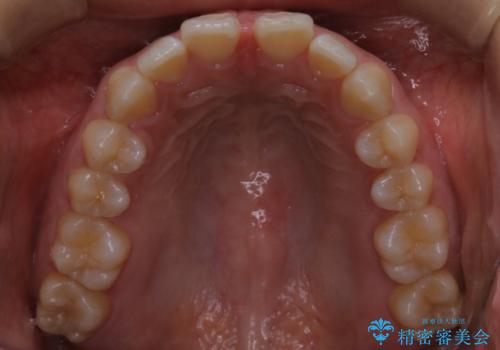

インビザライン矯正 前歯のすきっ歯を治したい

- 上顎の前歯のすきっ歯を治したいとのことで来院されました。

前歯の隙間を閉じる矯正治療の場合、インビザライン適用症例のためインビザラインによる治療をご提案しました。

後戻り防止のため、上唇小帯切除も併用しています。

上唇と歯ぐきを結ぶひも(上唇小帯)が長いと、前歯に隙間が空いてしまうことがあります。今回は隙間を確実に閉じる目的、また矯正後に再び隙間が空かないように、上唇小帯の切除も行っています。